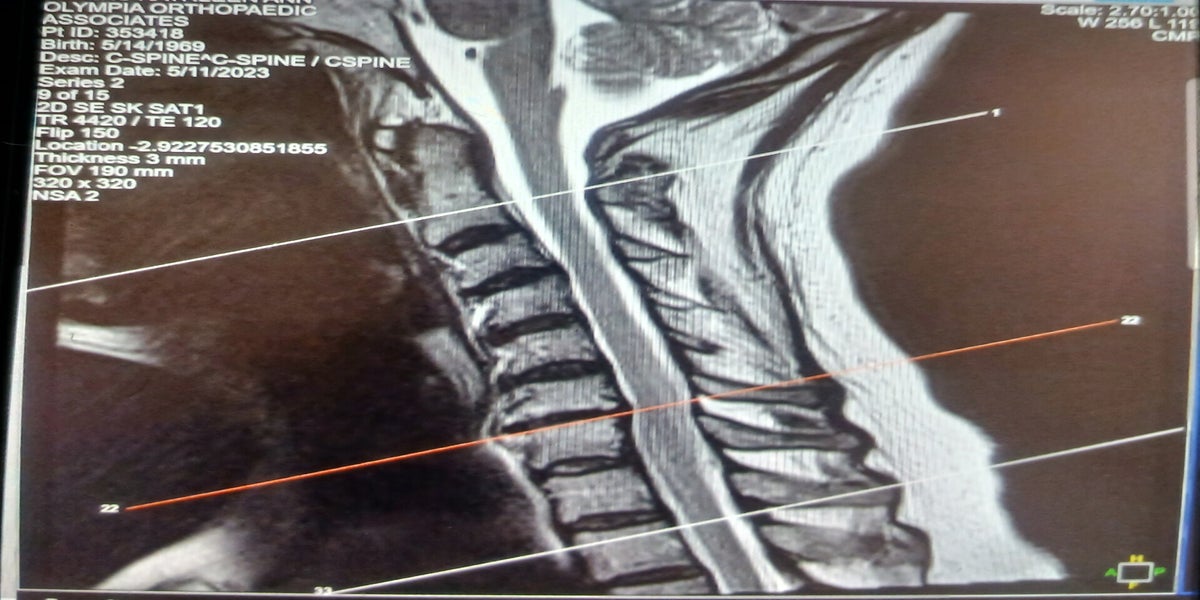

I worked in the capacity of a receiving supervisor. Many days this position required me to do heavy lifting and unloading trucks on my own. When there were things that needed more than one person to complete the job safely I would have to seek assistance outside of my department as there was typically only one person staffed within that department at a time or if there were two, the other person would be out offloading outside or off to lunch. On this particular day I was the only one in my department, there were many call outs that day and not many people to assist in any areas of the store. In this time I also carried keys for the store and I would cover as the Manager on Duty when the Assistant Store Manager would leave for lunch. On this particular day it was a perfect storm of destruction, the destruction of what I had been working toward for a very long time. I had already unloaded a quarter of the merchandise from the trailer of the semi. This particular semi trailer had slats that were in the ceiling that the tie down straps would be used to secure partial freight loads. This particular load was packed full. There is a rule that there should be a certain amount of headspace (the distance between the freight and the ceiling) in this load they had not followed the headspace rule. I was easily able to offload what freight was there until I got to that point where there were appliances stacked on appliance and a flooring underlayment box crammed between the top appliance box and this ceiling with the channels in it. I hopped on the slipsheet (equipment similar to a forklift, with a thinner sheet of metal that slides easily beneath appliance boxes) to offload them. When I slipped the metal plate beneath the appliances, lifted the tip of the plate, and Began to pull back, the appliances began tipping. Knowing that I would get an instant write up if the appliances fell I stopped right there, dropped the slip and pulled back. I reassessed the stacking and recognized that the boxes were catching on those channels. I checked to see if it was possible to pull out the freight surrounding it and the way it was structured would be impossible to remove without causing loose freight to topple. I hopped on the slipsheet again and tried to insert the slip between the underlayment and the top appliance to no avail. I hopped off the equipment and studied the packing of the freight again and noticed the issue with the ceiling tiedown channels. I grabbed the yellow ladder expressly provided for offloading freight and tried to pull the top box off, as it was crammed in there I recognized that I would need assistance pulling it out as doing it myself would be unsafe. I sought assistance from other departments and was on a timed offload so I was also under pressure to get my tasks completed prior to the freight teams arrival. I called the Assistant manager and requested help for safety purposes. He told me that he was busy but would send someone. I had already contacted other departments to request assistance but they were all busy as well and said they would assist as soon as they could. I continued to assess and re-assess what I could move in the mean time to keep my time management effective and could see nothing that would work without causing product damage or creating a safety issue for myself. I grabbed the yellow ladder again and tried removing the box, the yellow ladder had about a two foot by two foot platform with two steps up to the platform. The bottom of the box was at about eyebrow level to me and I had to reach up to be able to even attempt to move it. I tried to squeeze my fingers between the box and the other freight it was crammed between and I again didn't feel safe. I called the Assistant again and he yelled at me that he was busy and there was no one there to help. I told him it wasn't safe, I had tried everything, looked at every angle and that I was going to get hurt. He yelled at me again and said "You're a supervisor, figure it out!" I hung up the phone and went back to trying to get the box out, frustrated with the lack of support when I expressed the safety concern. I climbed the yellow ladder again and thought if did it real slow then maybe it would work, I squeezed my fingers between the boxes again and started inching the box out little by little, the top of the box kept catching on the channels and I had to bend my knees so I wouldn't fall off the ladder. The as the box slipped free from the bottom the top corner went up into the channel and the bottom swung down hitting me in the forehead knocking me off balance. Instinctively I pushed up with my core to regain my balance forgetting that I had been bending my knees so the box could clear the top of my head. My head went up into the box and it didn't give, my neck did. It felt like a stack of crackers being crushed, I heard it, I felt it, it felt instantly like little shards of bone scattered within my neck, I was positive that my neck had shrunk at least an inch in that moment, my stomach had dropped, I took stock, yes, I could feel my feet, my legs and obviously my arms as I was still holding the box. I was stuck, I couldn't escape the situation unless I got the box out. I knew nobody was going to be coming back to help me. I thought, if I bent my knees a bit more maybe I could roll it past my head and just drop it. I felt very shaky and was just trying to take it slow, as I rolled the box the corner dug into the top of my head, rolling it yet again only pushing it down to the right side, another foreboding crushing sound, panic sets in, in that moment I bent my knees and tried to fling th box over my head and right shoulder, the box had hit my right shoulder and my right hand flung with it flinging my arm back, it literally felt like my shoulder blade scraped the bones of my ribs. Maybe a ripping sensation? I was so stressed about what I felt with my neck. I immediately called the Assistant manager again to tell him that I was injured and he hung up on me, so I called again and he yelled "I'm with a customer" and hung up on me again. I went out onto the floor and found him right away straight down the aisle talking to another Supervisor. I went up and told him I was hurt. He turned around and said "Well, you should have been more careful, is receiving done yet?" I turned around and went back to receiving, my neck on fire. I started pulling the conveyors out and instantly I could feel the burning of my shoulder, I pushed the pain out of my mind and just tried to finish so I wouldn't get written up. Following, I went home and just went to bed. The next day I woke up and could not turn my neck at all, it was burning worse than the evening before. I drove to work and immediately went to my Supervisor and told her what happened, she asked why the other assistant didn't fill out paperwork and I told her that I didn't know, I told him, and all he told me was that I should have been more careful. She set about to complete the documention and had listed as a neck strain. I told her, it wasn't an incorrect lift, it was more than that, it was a "crunch" I told her I really needed to go get it checked out. She told me in a sarcastic voice, "oh, you're fine, it's just a neck strain. Take it easy and let your guys do the work" I reiterated that it was much more than that and I couldn't even turn my head, she responded that I had a team that day and I could just sit and do the paperwork. I felt defeated. I told the person that handled scheduling and human resources duties that I really felt like I needed to go to the hospital but I was told that I needed to do paperwork and that just by what happened, I knew I was going to have to eventually go in.